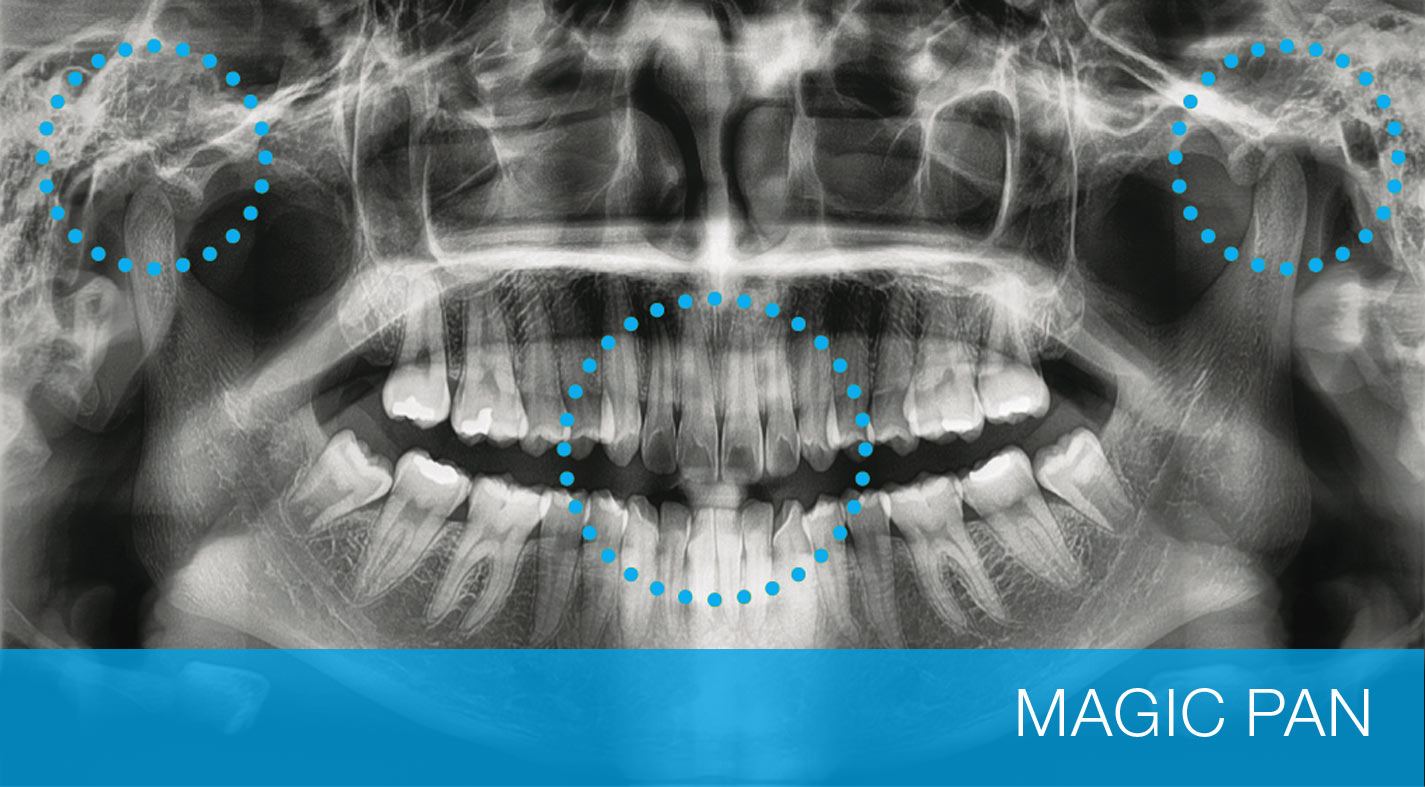

OTTIMIZZAZIONE DELL’IMMAGINE

CON IL SISTEMA MAGIC PAN

L’immagine a fuoco viene riorganizzata in tutto l’arco dentale, e la qualità d’immagine può essere aumentata. L’immagine diviene più chiara, specialmente nella regione degli incisivi e dei canini, nelle zone dell’articolazione ATM e dei canali radicali.